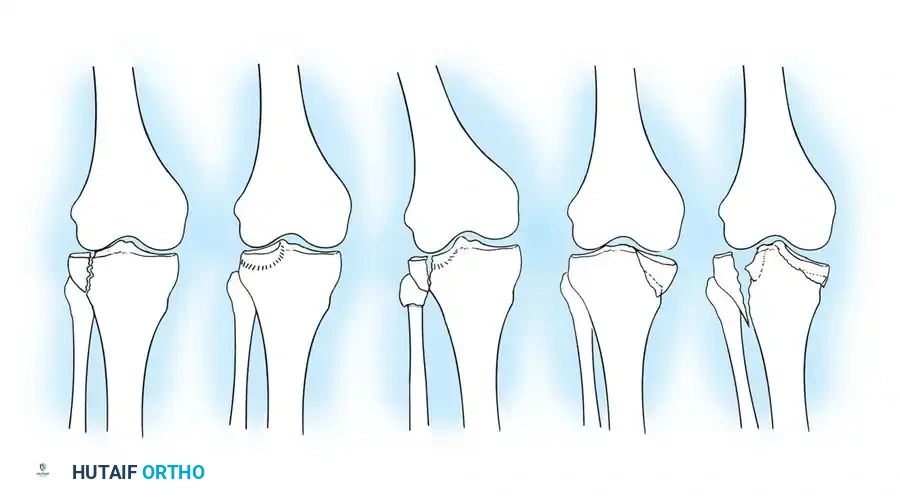

لتوحيد لغة التخاطب الطبي وتحديد خطة العلاج المثلى، يعتمد جراحو العظام على أنظمة تصنيف عالمية. من أشهر هذه الأنظمة تصنيف هول ومور وتصنيف شاتزكر.

تصنيف هول ومور للكسور المفصلية

يقسم هذا النظام الكسور إلى أنماط أساسية وأخرى مصحوبة بخلع.

تصنيف هول ومور لكسور هضبة التيبيا

تشمل الأنماط الأساسية الكسور ذات الإزاحة البسيطة التي قد تعالج تحفظيا، والكسور الانخسافية الموضعية، والكسور التي تتضمن انقساما وانخسافا في نفس الوقت، وصولا إلى الكسور التي تشمل كلا الجانبين من الهضبة.